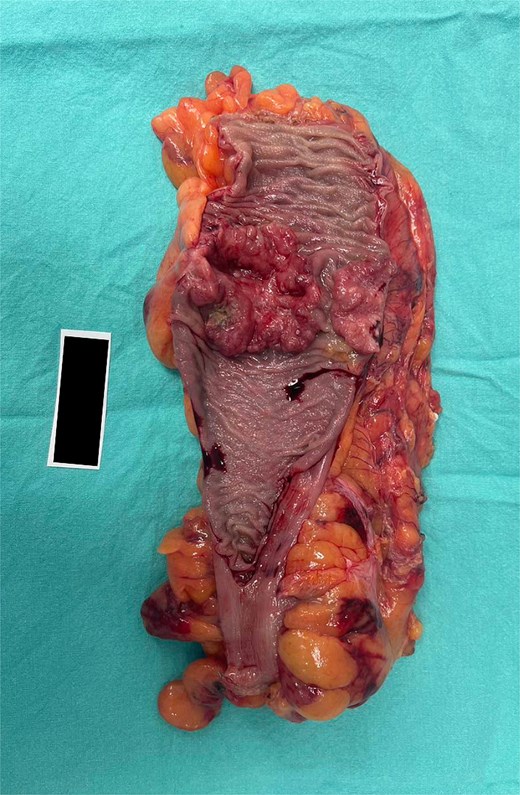

The mass in the kidney turned out to be at the midpole of the right kidney. The colon mass turned out to be an 80% circumferential sigmoid mass with a proximal margin of 15 cm and a distal margin of 10 cm. There were also several IMA nodes ranging from 0.5 to 1 cm (Fig. 6).

Surgical specimen from case 2 demonstrating sigmoid colon cancer.

The pathological analysis of the kidney mass was revealed to be ccRCC, measuring 6.0 × 4.7 × 3.5 cm with a histologic grade of G2. The tumor extension was limited to the lower pole of the right kidney. All margins were negative for invasive carcinoma, and 10% tumor necrosis was identified. In this case, the TNM staging of RCC was classified as T1bN0M0 [8]. The sigmoid colon mass was revealed to be grade G2—moderately differentiated, adenocarcinoma measuring 5 cm at the maximal diameter (Fig. 7). The cancer has shown invasion through the muscularis propria into the pericolic fatty tissue. Fortunately, the proximal resection, distal resection, and mesenteric resection margins showed no involvement by the invasive carcinoma. In addition, all of the 15 biopsied lymph nodes showed no metastasis. In this case, the sigmoid colon cancer was staged as T2N0M0 [9].